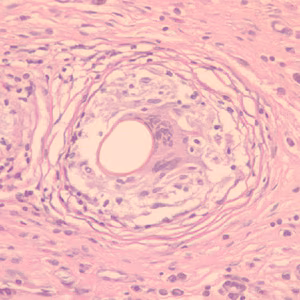

Eggs of Paragonimus spp. in tissue.

Diagnosis is based on microscopic demonstration of eggs in stool or sputum, but these are not present until 2 to 3 months after infection. (Eggs are also occasionally encountered in effusion fluid or biopsy material.) Concentration techniques may be necessary in patients with light infections. Biopsy may allow diagnostic confirmation and species identification when an adult or developing fluke is recovered.